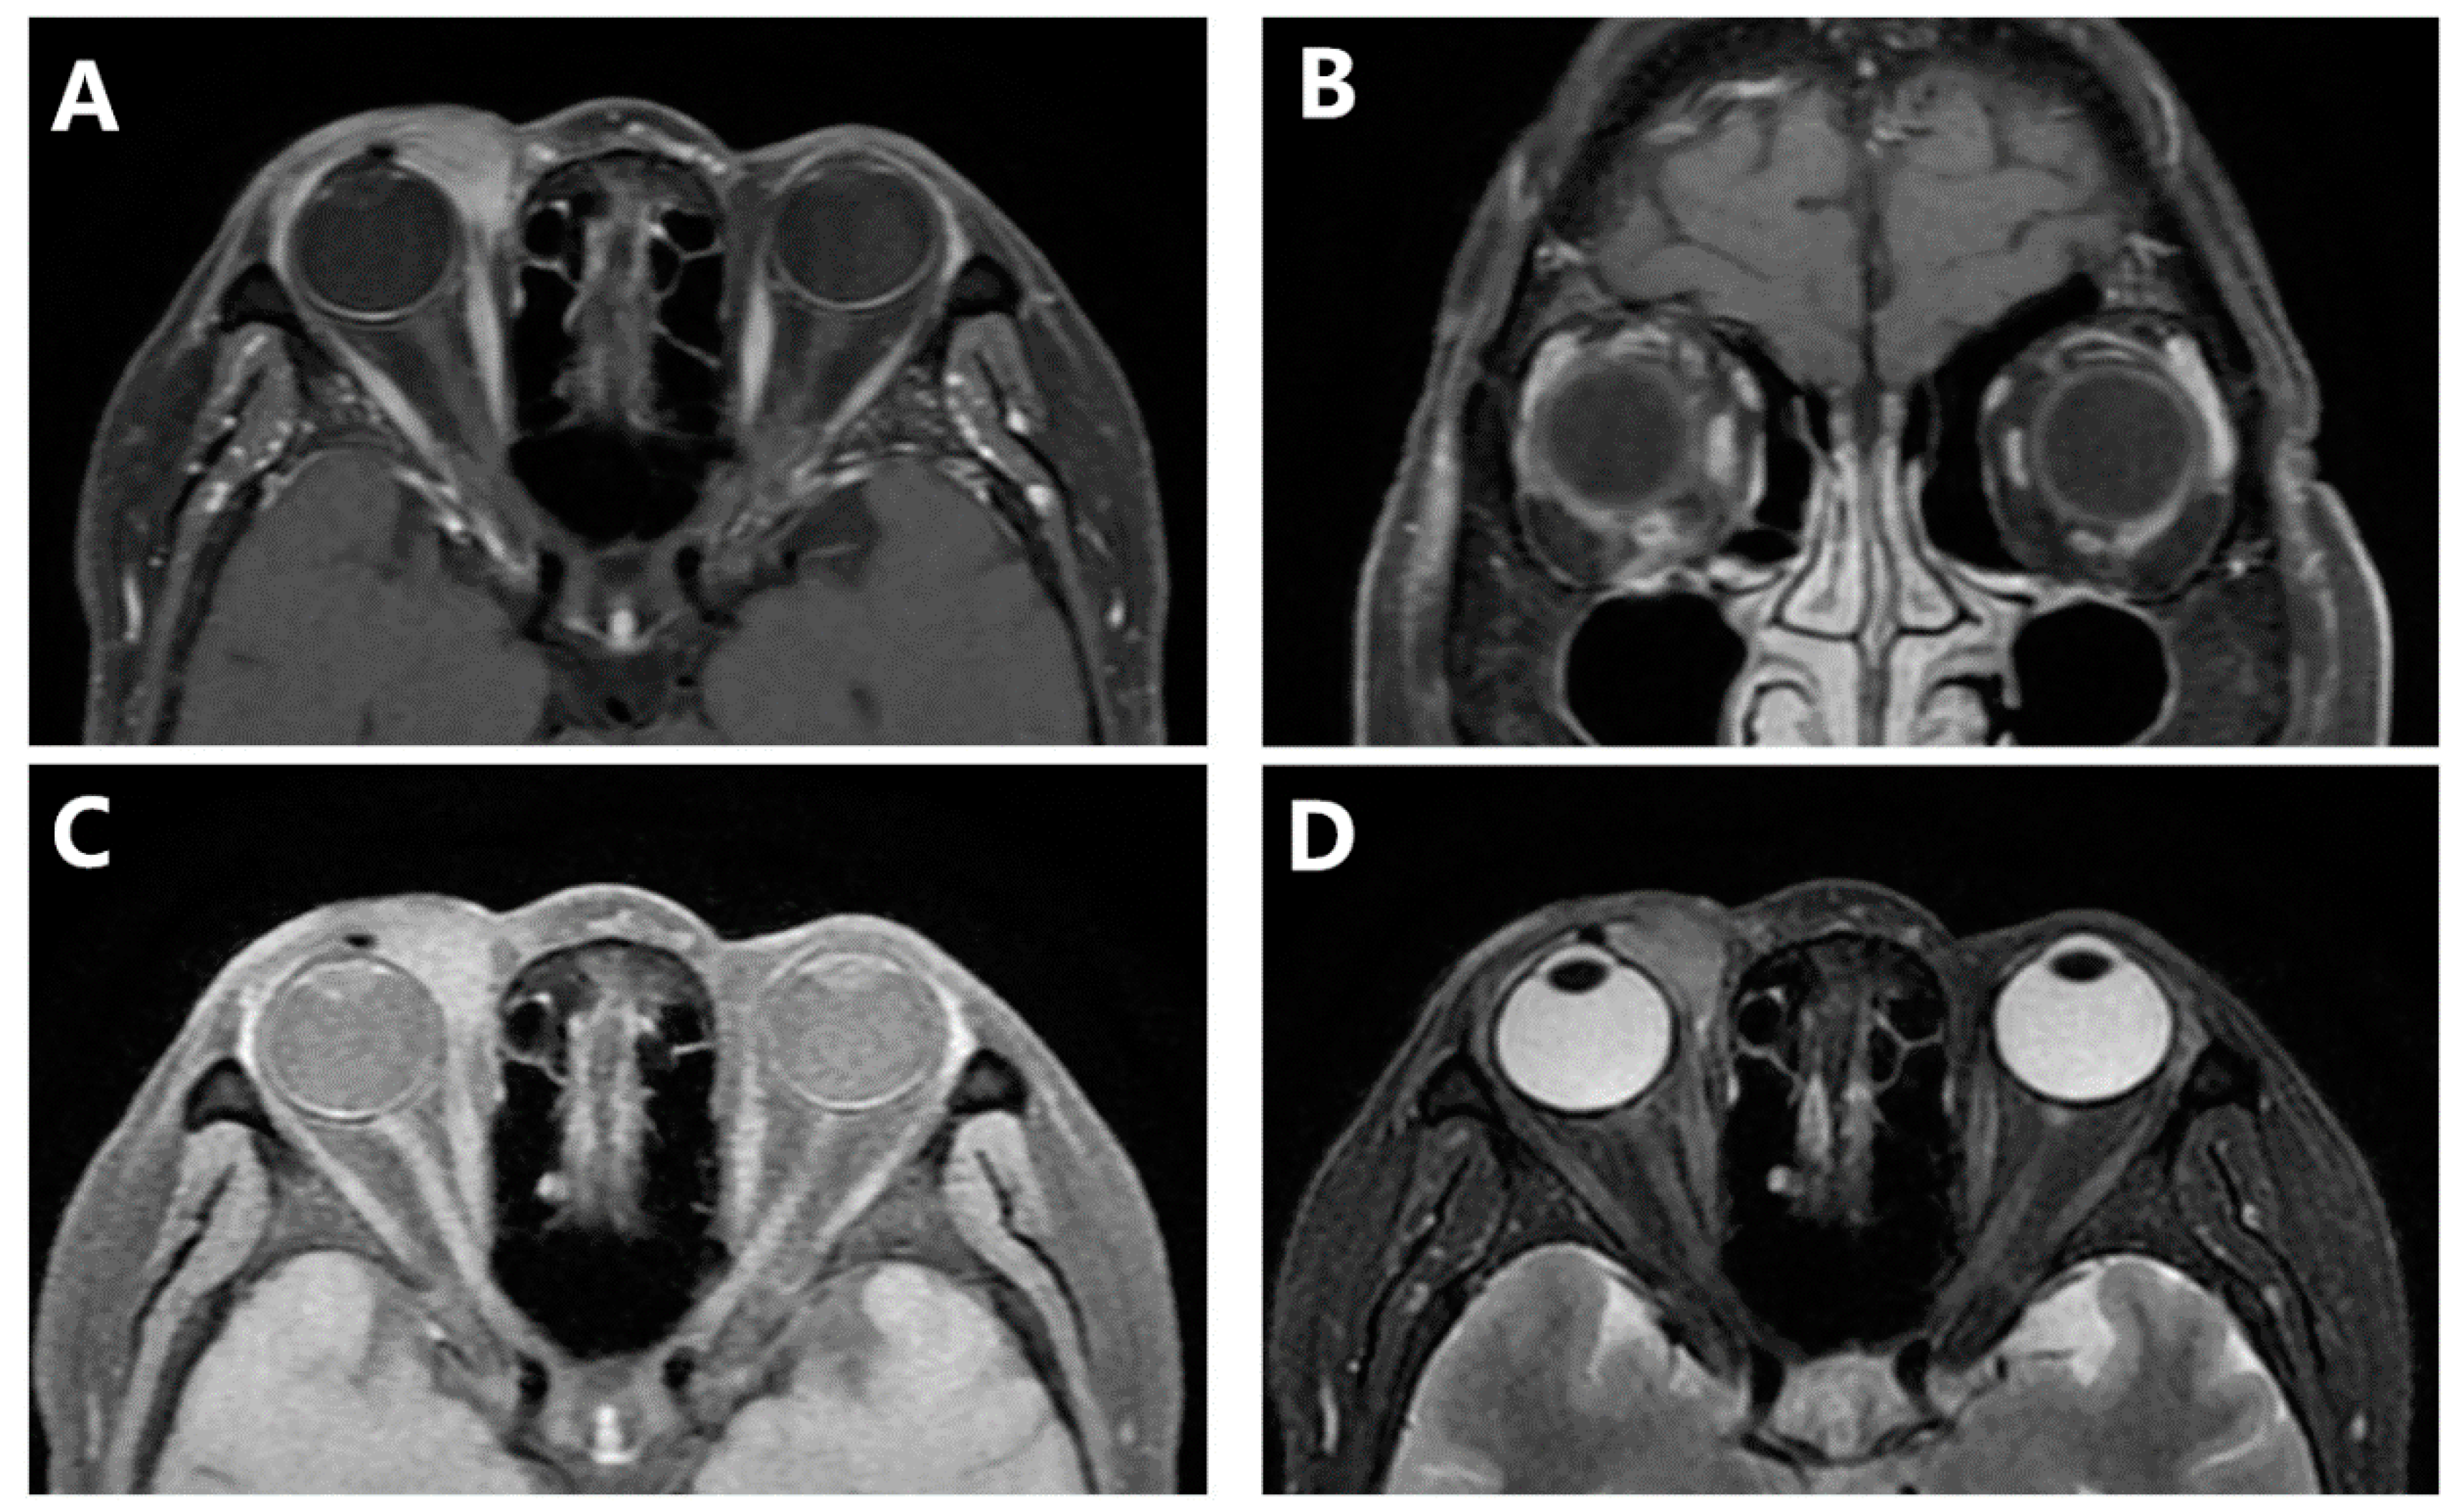

2. Case Presentation